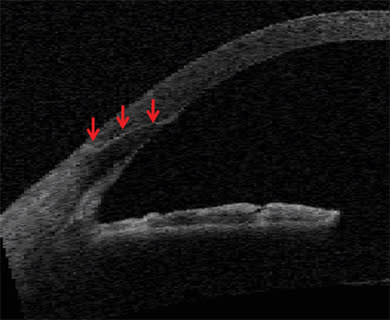

The femtosecond laser enables precise cuts that have important safety and performance implications both peri-operatively and long term. Integrated imaging systems, such as on-board OCT, provide registration to direct the laser both laterally and in depth (Figure 1). For clear corneal incisions, the OCT can provide the corneal thickness at the desired incision location so the architecture for incisions can be properly customized for each patient (Figure 2). This can include the main cataract incision sized for surgical instrumentation, such as the phaco tip and lens injector, and is designed for a watertight seal. It can also include side port incisions. The depth and architecture for relaxing incisions can also be registered, calculated and accurately delivered on the desired axis.

Figure 1. OCT detection of dimensions of anterior chamber and position of anterior and posterior capsule with physician-directed placement of capsulotomy and lens softening-segmentation cuts. Real-time OCT detection of anterior and posterior surfaces of cornea (blue arrows), anterior surface of the lens (red arrows), posterior surface of lens (yellow arrows), planned position and diameter of anterior capsulotomy (white arrows), and the position and depth of the lens segmentation and softening (green arrows).